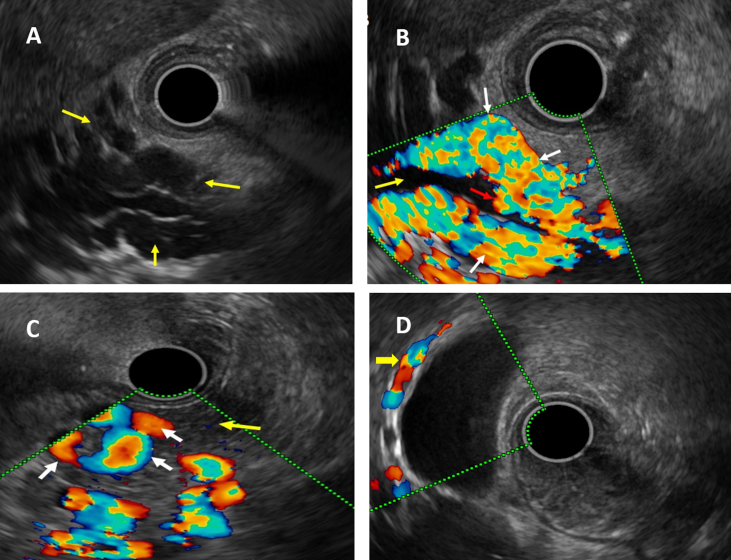

Endoscopic ultrasound changes

The distribution of EUS biliary changes are summarized in Table 1 and representative images in Figure 3. Presence of intracholedochal collaterals had significant association with type of block (P = 0.002), with higher frequency of these collaterals in children having PV block extending either into SV, SMV, or both. Similarly presence of intrapancreatic collaterals were seen more frequently in children having accompanying SMV block (P = 0.04). Intramural GB collaterals on EUS and pericholecystic collaterals on MRC were seen in a similar number of patients (39 & 46 respectively; P = 0.36). On further analysing patients with intracholedochal collaterals (n = 5), intramural GB collaterals (n = 39), and intrapancreatic collaterals (n = 40), no significant associations were seen with the MRC changes like extrinsic compressions, cholelithiasis, CBD strictures/narrowing, or intrahepatic narrowing/strictures. We found that para-pericholedochal collaterals, wall thickening of GB, intramural GB collaterals, and intrapancreatic collaterals had significantly higher frequency of occurrence in children having Llop grade 3 MRC changes (P = 0.004, 0.009, 0.03, and 0.03, respectively). The clinical, biochemical, radiologic, and EUS biliary findings in different modified MRC Llop severity grades is shown in Table 2.

Figure 3.

(A–D): Endoscopic ultrasound (EUS) images showing various collaterals in children with portal cavernoma cholangiopathy. A: EUS image showing multiple anechoic, tubular structures at porta (yellow arrows); B: colour Doppler EUS image of the same patient showing para-pericholedochal collaterals (white arrows) around the common bile duct (yellow arrow) and intracholedochal collateral (red arrow); EUS colour Doppler images showing C: intrapancreatic collaterals (white arrows) in the pancreatic parenchyma (yellow arrow); D: intramural gall bladder collaterals (yellow arrows).